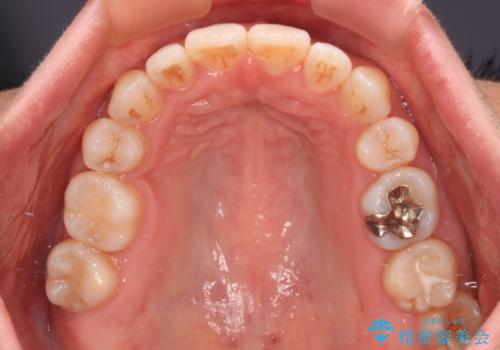

骨格的な左右差があり、上下正中をぴったり合わせることは難しく、奥歯の咬み合わせの調整にも時間がかかりましたが、きれいに整えることができました。